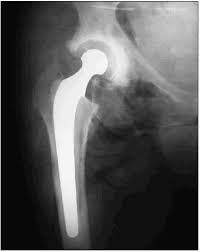

Artroplastia total de cadera

Artroplastia total de cadera. Es la sustitución, tanto de la cabeza femoral como del acetábulo, por encontrarse éstas en un deterioro tal que provocan un cuadro de sufrimiento articular que no es reversible por otros métodos conservadores o quirúrgicos menos agresivos.

Componentes de una prótesis de cadera

- Componente femoral: esfera o cabeza que va unida a un vástago o tallo.

- Componente acetabular: una cazoleta hecha de plástico especial (polietileno).

- El componente femoral está hecho de metal (actualmente algunos tienen cerámica que encaja en el vástago).

- El componente acetabular esta hecho de una concha de metal que se sujeta al hueso por varios sistemas y contiene en su interior una porción de plástico que actúa como soporte.

- La [[prótesis[[ cementada se mantiene en su sitio mediante un tipo de cemento epoxídico que fija el metal o el plástico al hueso.

- Una prótesis no cementada tiene algún sistema (malla, poro, hidroxiapatita) en su superficie que permite que el hueso crezca en él y fije la prótesis.

Estudios de imagenología

En la radiología simple de ambas caderas en vista AP, se puede valorar el estado radiológico de estas y comparar la afecta con la sana. Se pueden indicar, si fuese necesario, las pruebas de Pawells.